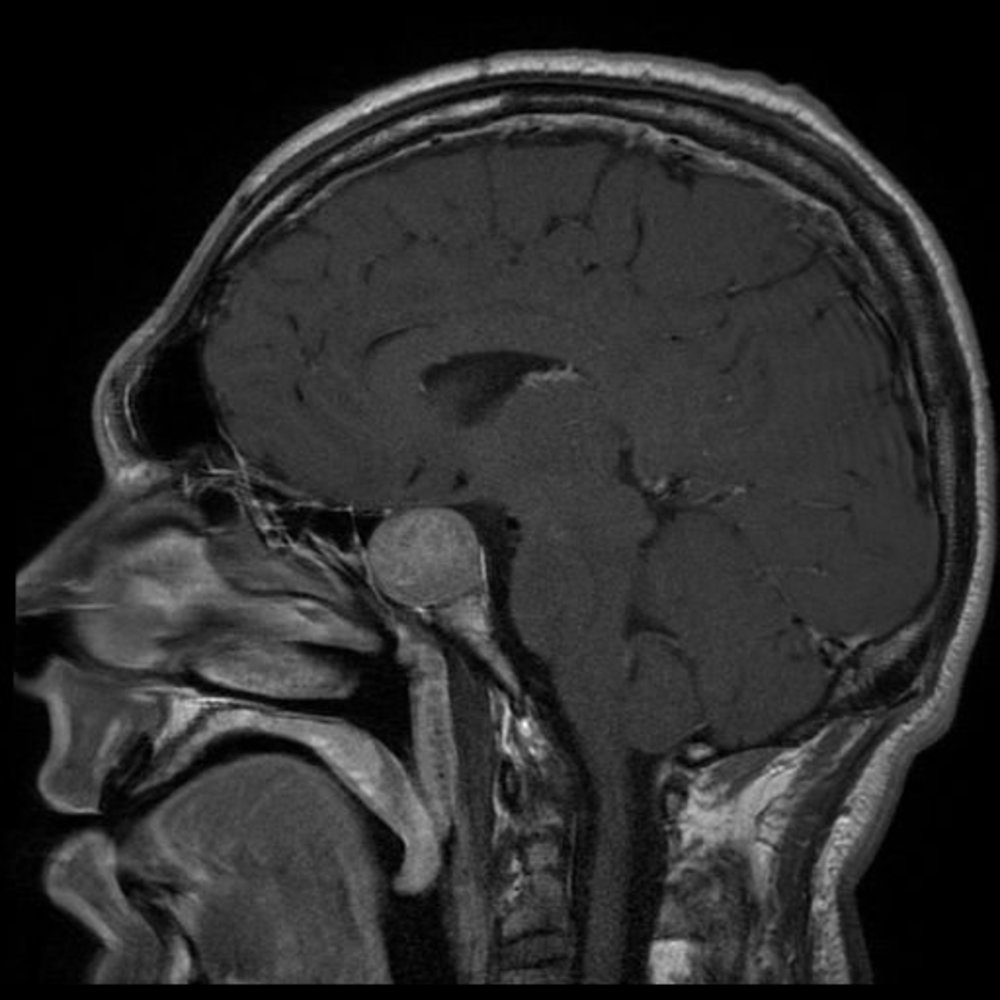

Imaging [12]

Imaging of the pituitary is indicated in all patients to determine the underlying cause.

• MRI brain

• Preferred imaging modality

• Findings depend on the underlying etiology and include pituitary adenomas (most common cause in adults), congenital malformations, and trauma.

• CT Head (without IV contrast): used if there are contraindications to MRI or in patients requiring rapid evaluation, e.g., after suspected TBI or SAH